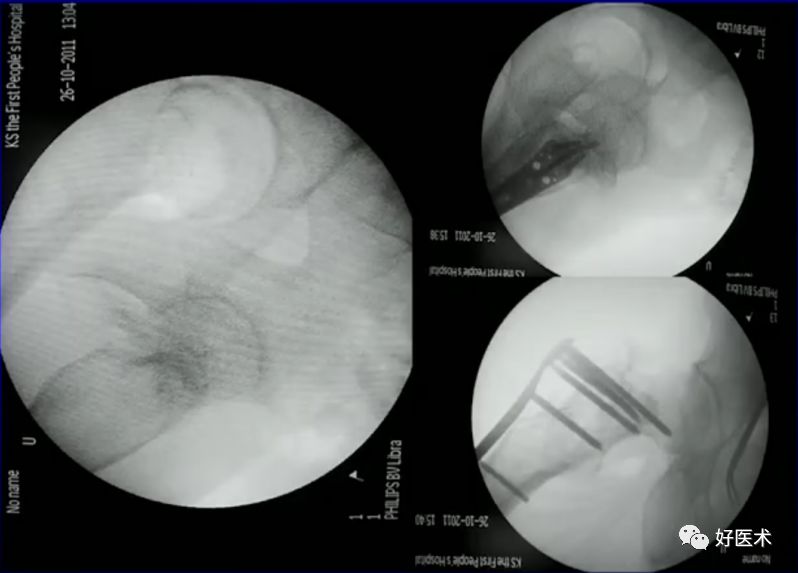

病例三:女 82岁

四部分骨折,髓内钉,钢板

病例:男,34岁,高处坠落伤,仅骨折余正常

处理方法:

-

髓内钉(开放VS闭合)

钢板

其他

术前牵引

开口、定位

术中过程